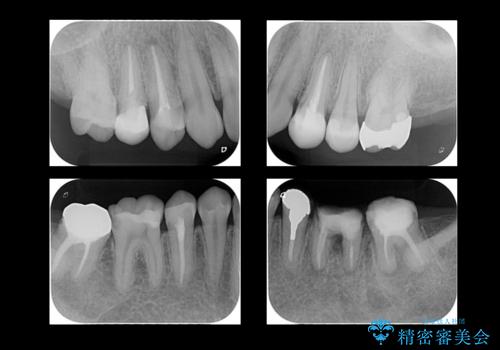

全体的な虫歯治療

- 左下の虫歯を主訴に来院。

全体的に虫歯もあったため治療を行いました。

左下のブリッジについてフォーカスしたものは以下をご覧ください。